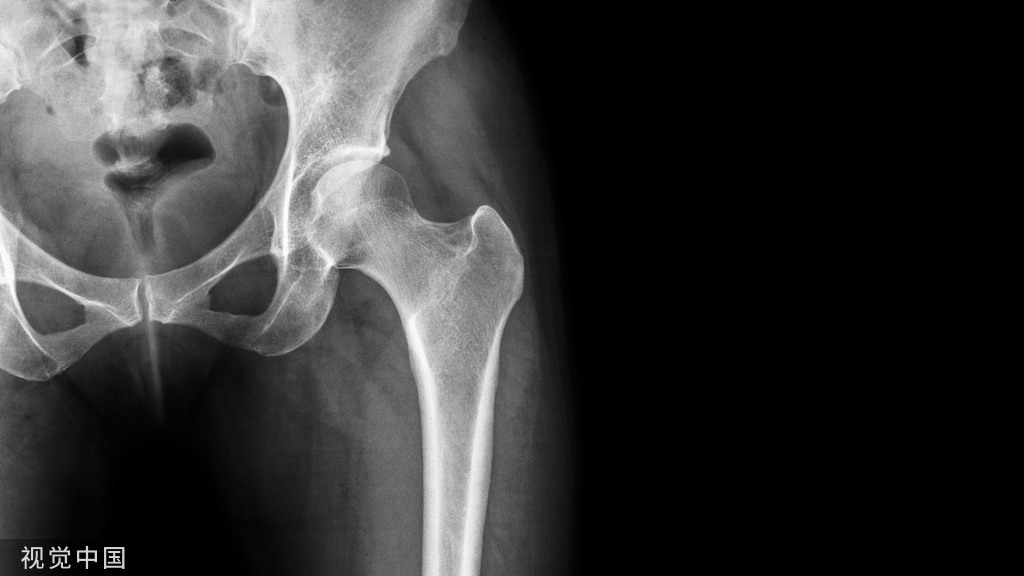

受伤后有些人会选择保守治疗,有些人会选择手术治疗,毋庸置疑的是大多数人都会有形成疤痕。我们最常听到的就是患者说动关节的时候粘住了,我们去思考一个问题,到底怎么样才能把疤痕粘连松开和松开后就真的好了吗?

当我们的软组织(肌肉、肌腱、韧带、筋膜…)因为过度使用、过度操劳,承受反复损伤(压迫、拉扯、扭转…)而微小出血,在伤口周边不停产生新的疤痕。而这些疤痕会再与旁边的组织相黏,这些疤痕不一定会顺着软组织原本的方向生长,而使得他们无法正常发挥作用,包括觉得使不上力、拉扯会不舒服、强度下降,严重者甚至会影响关节活动。